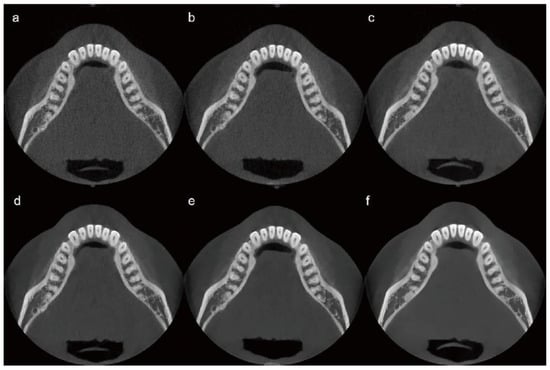

A single-subject, intra-individual study design was employed to enable direct comparison of CBCT images acquired under different radiation dose conditions while minimizing anatomical variability. The use of a single healthy adult male without maxillofacial pathology provided a consistent anatomical reference, allowing controlled assessment of technical image quality changes associated with dose reduction and AI-based post-processing. This approach was selected for this exploratory feasibility study to support consistent visual comparisons across dose levels while adhering to the ALARA (As Low As Reasonably Achievable) principle by limiting unnecessary radiation exposure. The limitations inherent to a single-subject design are acknowledged and are addressed in the Discussion. Scans were performed at three radiation dose levels: 10%, 20%, and 100% of the standard clinical dose. These initial scans, referred to as “raw images,” were not subjected to AI processing. Each raw image was subsequently processed using an AI-based image enhancement algorithm, resulting in three additional image sets termed “AI-processed images.” Six image sets were thus prepared and categorized according to the radiation dose level and AI processing status as follows: Image 1 (10% dose, raw image), Image 2 (10% dose, AI-processed), Image 3 (20% dose, raw image), Image 4 (20% dose, AI-processed), Image 5 (100% dose, raw image), and Image 6 (100% dose, AI-processed). CBCT was performed using a Bright CT scanner (Dentium; Suwon, Republic of Korea).

For the 10% dose image set, the parameters were 85 kVp, 8.5 mA, and 16 ms, resulting in a DAP of 193.38 µGy·m2. For the 20% dose image set, the parameters were adjusted to 85 kVp, 9 mA, and 16 ms, yielding a DAP of 386.77 µGy·m2. The detailed CBCT scanning protocols, including kVp, mA, ms, and DAP, are summarized in Table 1. Representative images from each protocol are shown in Figure 2.

Figure 2.

CBCT image sets categorized by radiation dose level and AI processing status. (a) 10% dose, raw image; (b) 20% dose, raw image; (c) 100% dose, raw image; (d) 10% dose, AI-processed image; (e) 20% dose, AI-processed image; (f) 100% dose, AI-processed image. AI, artificial intelligence; CBCT, cone-beam computed tomography.